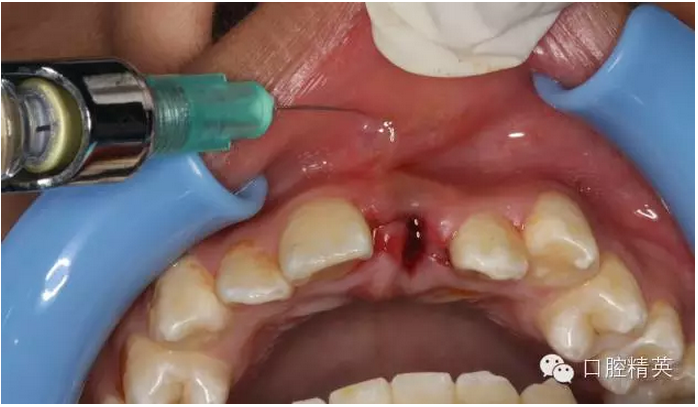

圖12.局部浸潤(rùn)麻醉

圖1.術(shù)前患者口內(nèi)像、牙槽窩輕度收縮、血凝塊穩(wěn)定、無(wú)滲出。